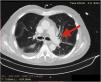

A 72-year-old man, previously independent, was admitted to the emergency department following cardiorespiratory arrest. A chest computed tomography scan (CTS) was requested. During the exam, the patient experienced sudden hypotension (65/20¿;mmHg) and poor peripheral perfusion. The exam was suspended and a fluid bolus was administered, resulting in transient reversal of the condition. Gas was detected in the injection system, which was replaced, and the exam was repeated. The CTS revealed gas embolism with an air-fluid level in the main pulmonary artery (marked with an arrow in Fig. 1), right atrium and right ventricle (marked with an arrow in Fig. 2), as well as in the left upper lobar artery (marked with an arrow in Fig. 3). Due to the venous gas embolism, he was transferred for treatment at a hyperbaric medicine center.